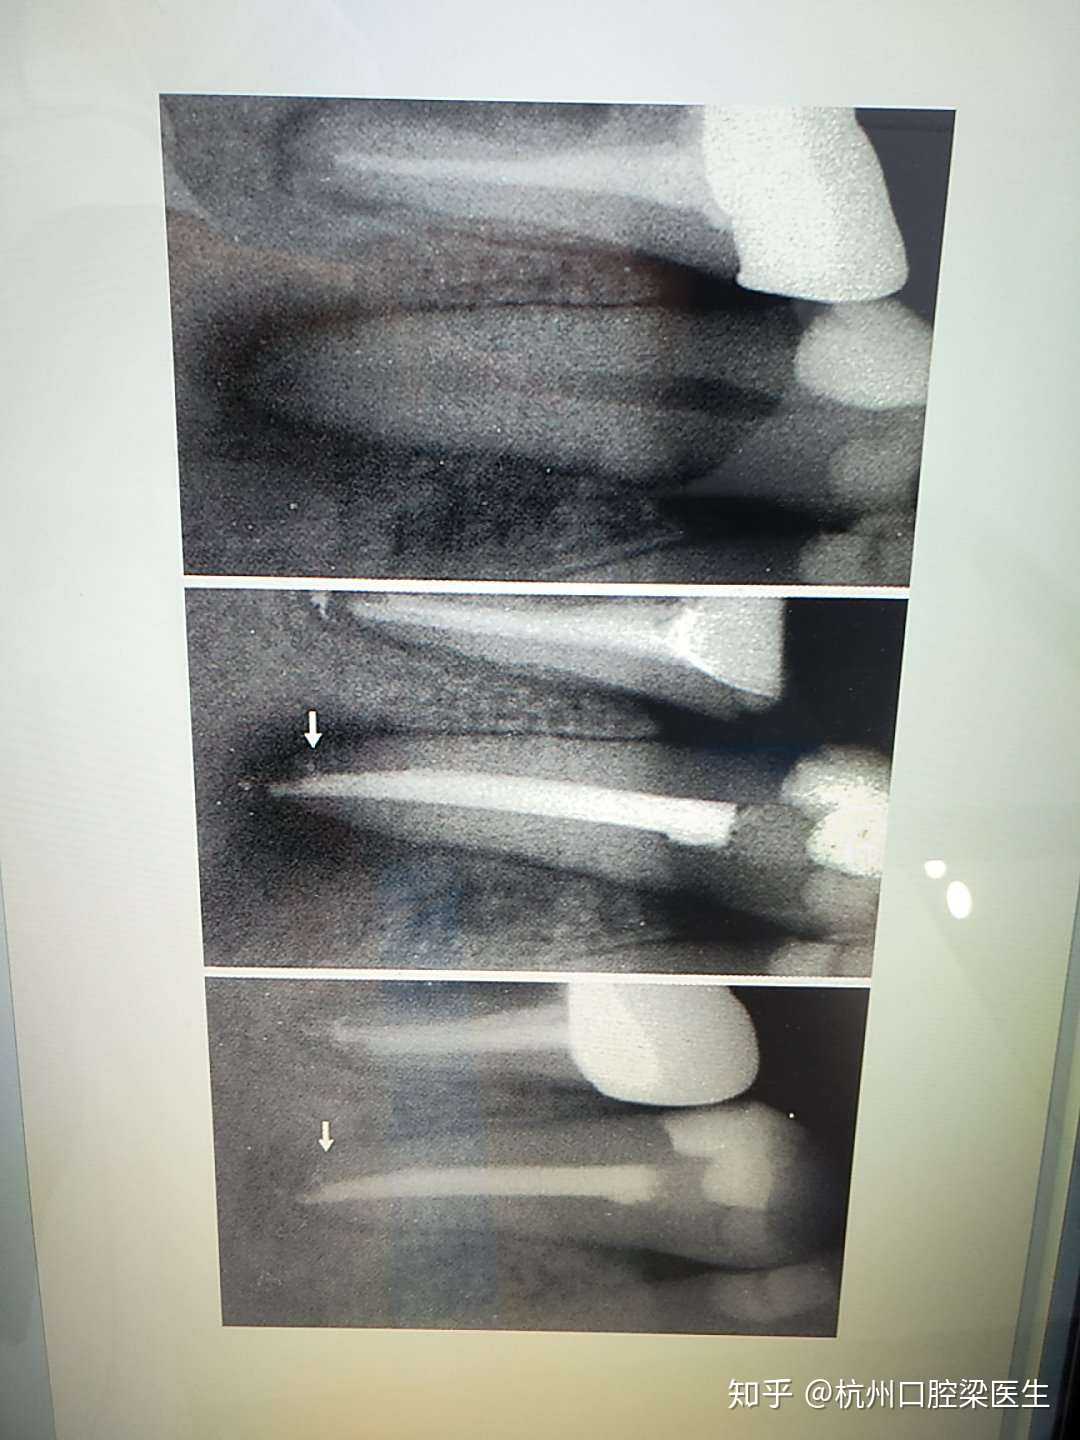

登录 杭州口腔梁医生 3 分享 举报 还没有评论 取消 评论 {"debug"